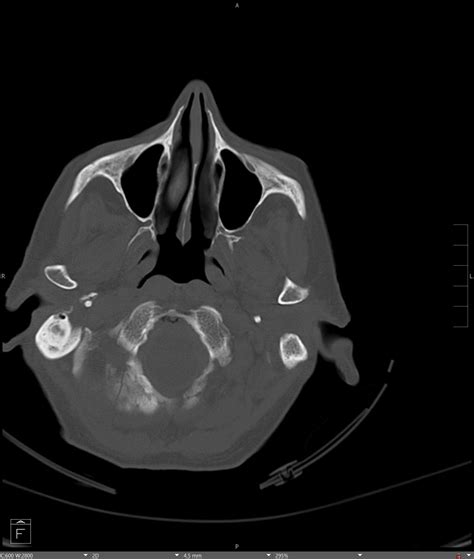

• Computed Tomography (CT) Scan: This is the gold standard for diagnosing occipital condyle fractures. CT scans provide detailed images of the bony structures and can help identify the location and extent of the fracture.